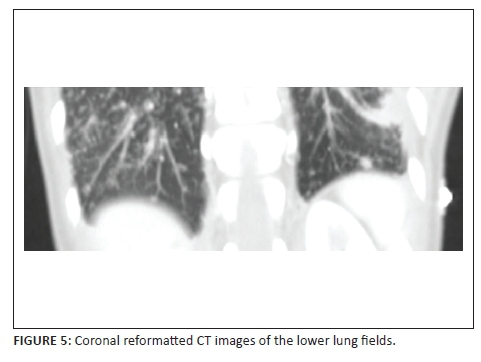

A 32-year-old lady presented with shortness of breath, (New York Heart Association [NYHA] grade 2-3), becoming progressively worse, associated with cough, chest pain and constitutional symptoms. She underwent extensive investigations shown in the series of images including chest radiograph, abdominal sonar, computed tomography of chest and abdomen as well as a cardiac magnetic resonance imaging study.

Describe the relevant imaging findings and formulate the most appropriate clinical diagnosis.